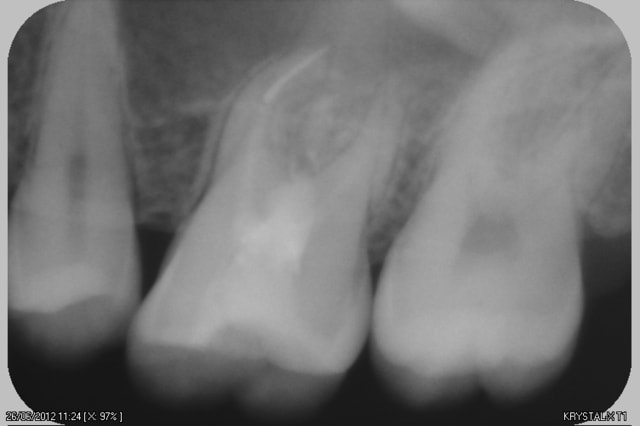

voila la radio

une limme cassé dans l'au dela

la patiente evoque une rhinorrhée depuis le traitement

L'instrument est cassé après la courbure, donc oublie les kits de retrait d'instrument (trop de délabrement, et surtout pas après une courbure!)

D'autre part, le traitement étant imparfait, il faudrait déjà reprendre le traitement et profiter pour faire un By Pass.

C'est la seule solution pour sauver cette dent.

ok avec scuba 06 by pass ou en passant par le mv2 si rejoint mv1 sinon davier